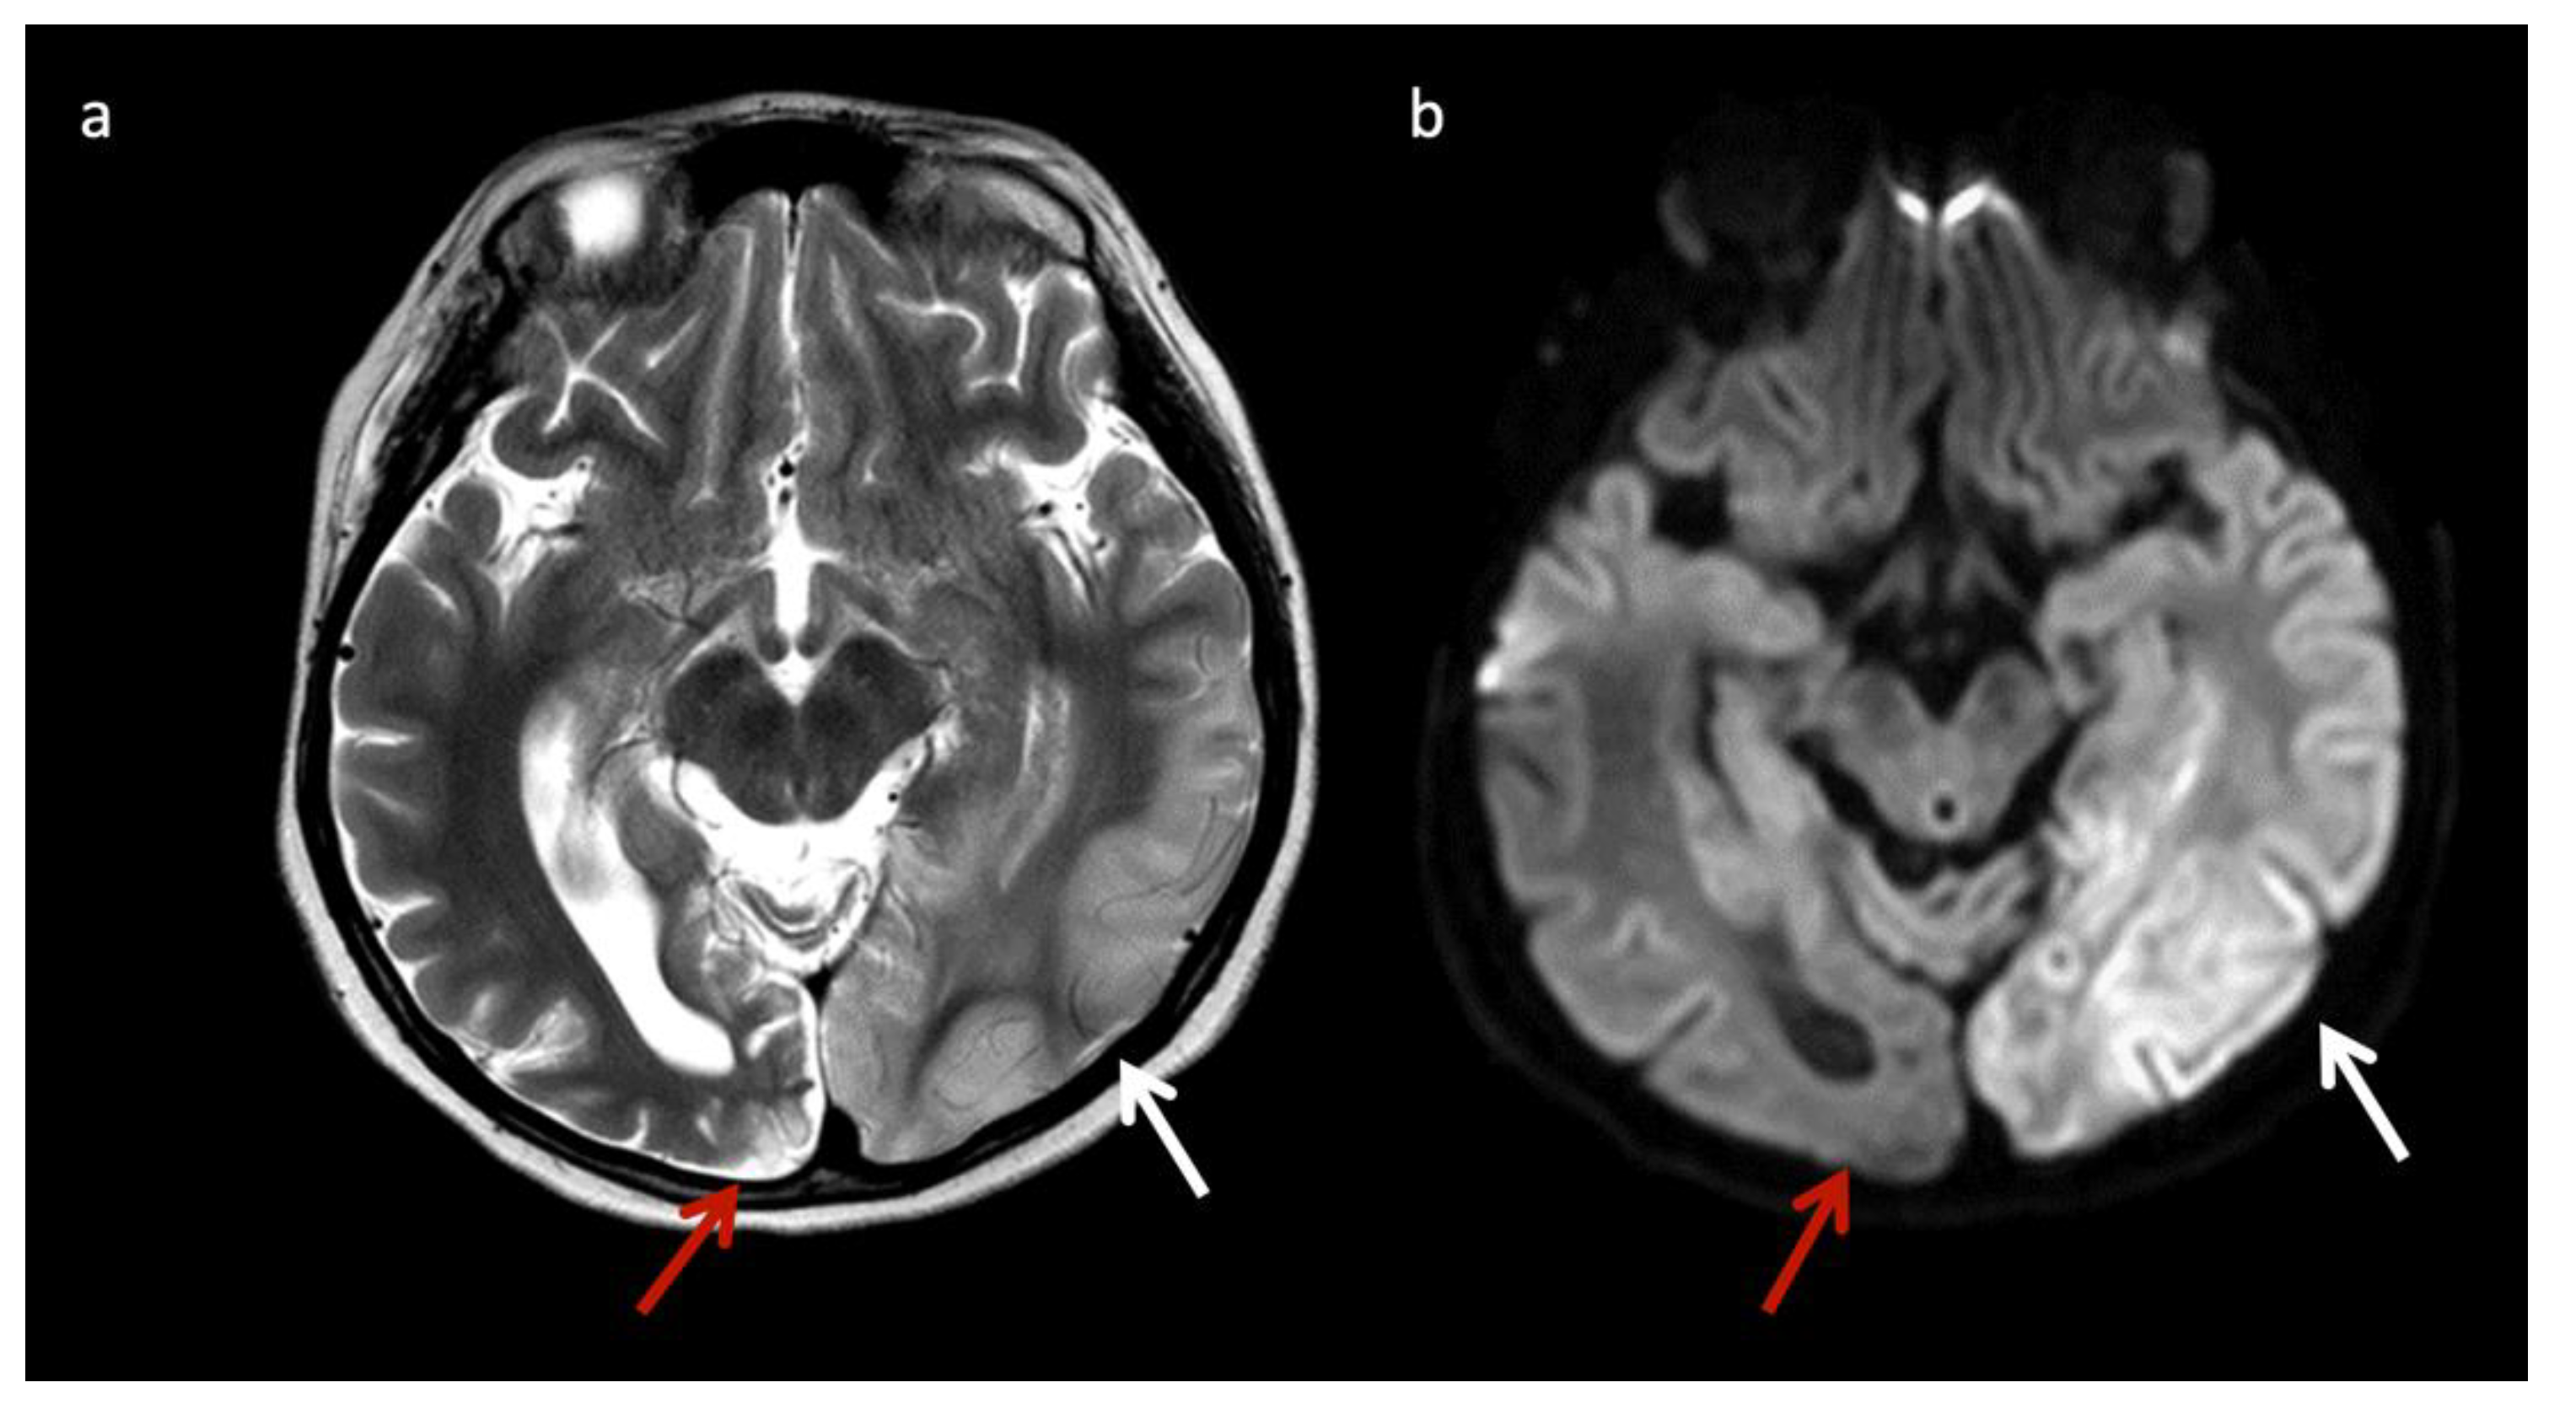

Mitochondrial encephalopathy with lactic acidosis and stroke-like episodes (MELAS) (Figure 4) may also have suggestive imaging features, with patients having non-vascular territorial metabolic stroke-like episodes [3]. Similar to MELAS, POLG-related mitochondrial disorders often cause nonterritorial cortical/subcortical edema/injury; however, perirolandic parenchyma and thalami tend to be more preferentially affected [19].

Figure 4.

Eleven-year-old male with new onset seizures and history of multiple stroke-like episodes attributed to mitochondrial encephalopathy, lactic acidosis, and stroke-like episodes (MELAS). (a) Axial T2WI and (b) axial DWI at the level of the midbrain show nonterritorial cortical/subcortical edema/swelling in the left occipito-temporal region involving both middle and posterior cerebral artery territories consistent with acute metabolic injury (white arrows). Volume loss, T2 prolongation, and facilitated diffusion consistent with encephalomalacia from old metabolic injury is noted in the right occipito-temporal region (red arrows).